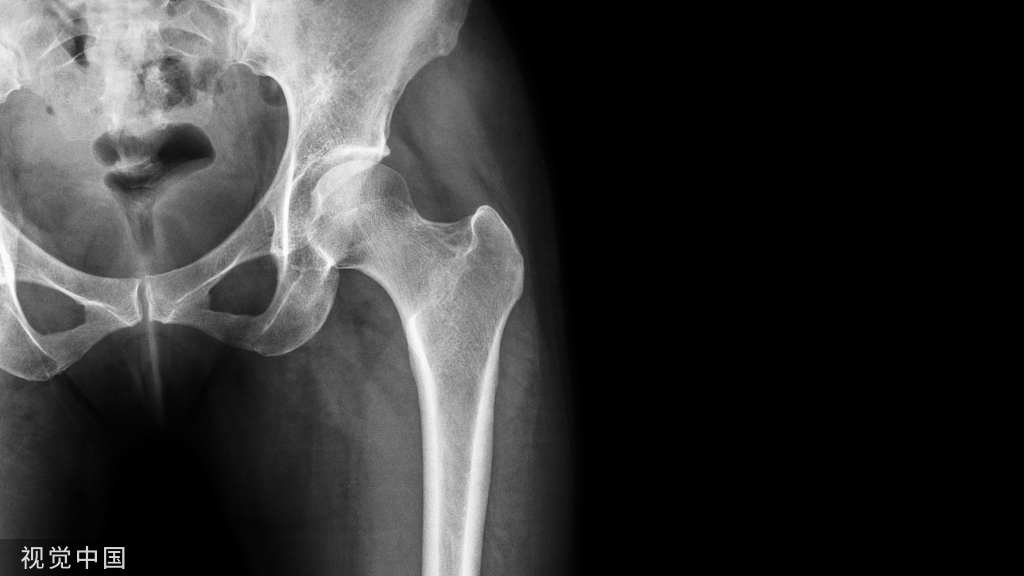

364例复杂骨盆骨折带你掌握内固定技术!